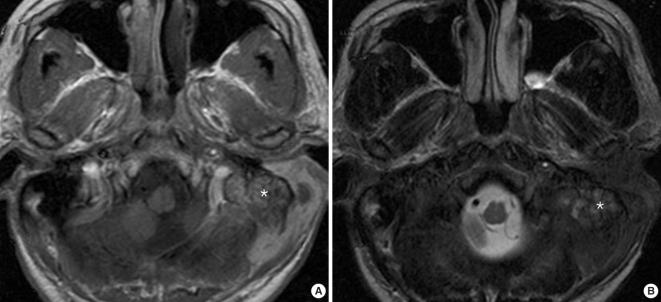

颞骨髓肉瘤。

Temporal bone myeloid sarcoma.

Myeloid sarcoma is a rare condition that's caused by the aggregation of immature myeloid cells in leukemic patients. Myeloid sarcoma occurring in the temporal bone more frequently involves the mastoid bone than is the case for metastatic lesions arising from non-systemic malignancies. The disease is difficult to diagnose when it presents with symptoms that mimic otomastoiditis. However, an early diagnosis is important in order to achieve complete remission of the disease. Magnetic resonance imaging of the temporal bone is useful for making the diagnosis of myeloid sarcoma, and especially to evaluate the extent of disease. High-dose radio- or chemotherapies are the first-line approaches and possibly the only approaches to achieve complete remission and to cure the disease. With the aim of improving our understanding of myeloid sarcoma in the temporal bone, the present report describes our experience with 5 such cases and we compare the clinical features of these 5 patients with those clinical features of patients who have metastatic lesions.

骨髓肉瘤是一种罕见的病症,由白血病患者中未成熟髓细胞的聚集引起。发生在颞骨的骨髓肉瘤比非系统性恶性肿瘤转移病变更常累及乳突骨。当疾病表现出类似于乳突炎的症状时,诊断较为困难。然而,早期诊断对于实现疾病的完全缓解非常重要。颞骨磁共振成像有助于诊断骨髓肉瘤,特别是评估疾病的范围。高剂量的放化疗是一线治疗方法,可能是实现完全缓解和治愈疾病的唯一方法。为了提高我们对颞骨骨髓肉瘤的认识,本报告描述了我们对 5 例此类病例的经验,并将这 5 例患者的临床特征与患有转移病变的患者的临床特征进行了比较。